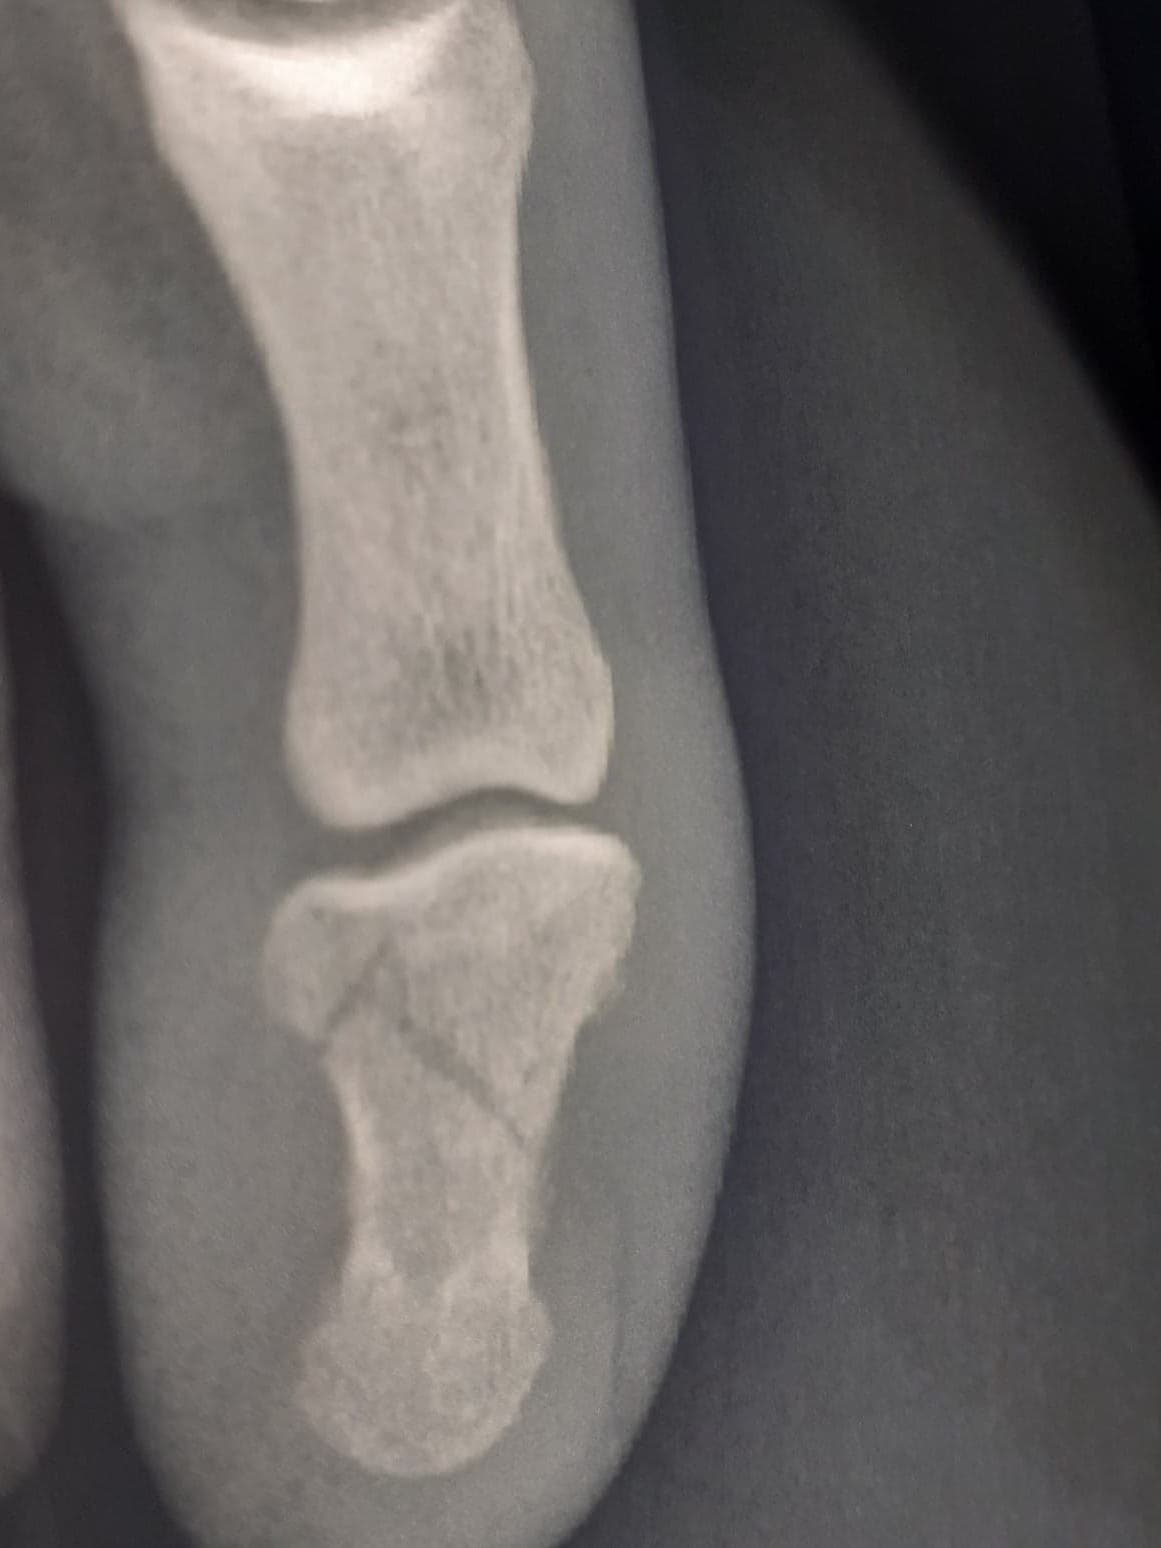

fracture P2.

Bobainko